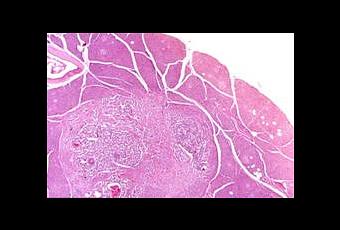

Los insulinomas son tumores generalmente benignos de las células excretoras de insulina del páncreas. Afecta a las células beta del páncreas, encargadas de la producción de insulina que el organismo necesita para el metabolismo de la glucosa. Habitualmente son tumores que afectan con mayor frecuencia al sexo femenino y cuyas edades oscilan entre los 40 y 50 años.

Los insulinomas son tumores poco comunes que se presentan en aproximadamente 1 de cada 250.000 personas. Estos ocurren usualmente como tumores únicos y pequeños en los adultos, del 5 al 10% de los insulinomas son malignos.